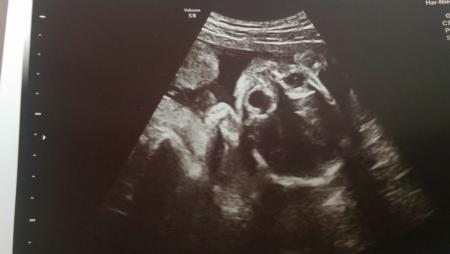

Danke für eure lieben Beiträge. Als kleines Dankeschön würde ich euch gerne das heutige Ultraschallbild von meinem Äffchen zeigen. Sie hat mir heute ein Bild mitgegeben, aber ich glaube, dass es das Schönste ist, was ich bekommen kann. < 3 Es sieht so aus als würde sie mir direkt ins Gesicht blicken. Einige finden das Bild vielleicht gruselig, aber ich bin unglaublich verliebt in sie. :) Ich hätte übrigens auch einen Jungen mit offenen Armen empfangen, aber ein Mädchen zu haben, ist für mich genauso schön. Es ist nur jetzt beruhigend zu wissen, was es wird. :)

Das ist ja ein cooles bild, meistens sieht man die kleinen ja nur von der seite. Da hast du ja heute einen glücksultraschall gehabt.

Ui wie schööön!!!!! Herzlichen Glückwunsch zur kleinen Krümelmonster-Prinzessin! Das Bild ist echt cool! :))))